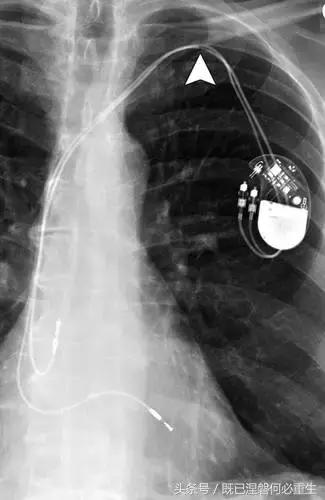

用于将导线的近端部分固定到胸壁的导线固定件可以模拟损伤。扎带是通常位于锁骨和发生器之间并且可以压接引线的套囊(图8A和8B)。熟悉这种外观和通常的射线透射束缚的位置可以防止错误报告磨损的线索。

图。 8A在两个不同患者中电极断裂的电极结合物的实例。

图。 8B在两个不同患者中电极断裂的电极结合物的实例。